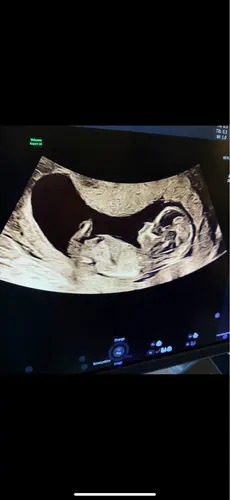

Ik vind het zo knap dat mensen hier wijs uit komen, ik kom er zelf maar niet uit, maar ben stiekem ook wel benieuwd of onze 2de een jongen of meisje is, kan iemand helpen? 😊

Alvast bedankt !

Duidelijk meisje!